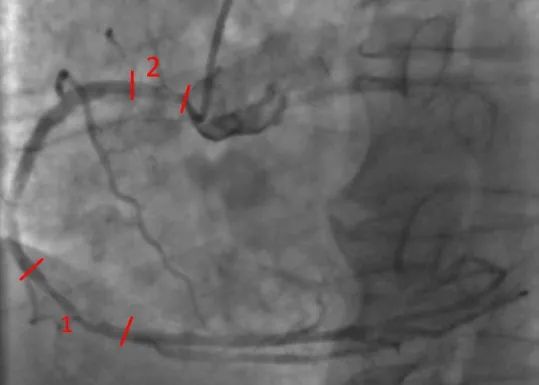

冠脉造影:

提示LM轻度病变,LAD中段局限病变并伴有钙化(图1);LCX远端局限病变(图2);RCA中段临界病变,开口处重度狭窄(图3)。